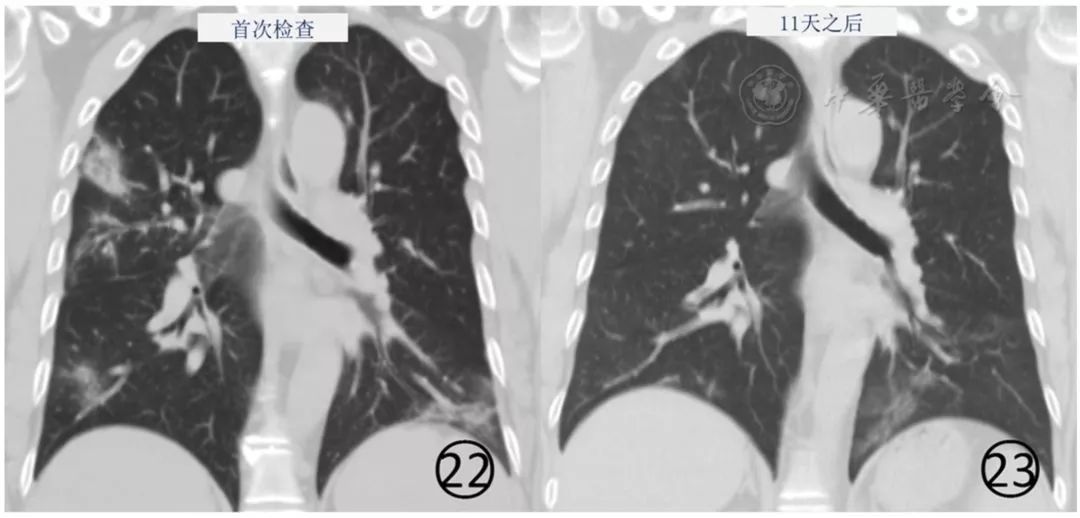

绝大多数新型冠状病毒感染的肺炎患者经过隔离治疗,病情趋于稳定、好转,表现为病灶范围缩小,密度逐渐减低,病灶数量减少,磨玻璃阴影可完全吸收(图22,图23)。

图22,23 男,48岁。基线(图22)CT平扫肺窗显示多发斑片状磨玻璃阴影和实变,治疗11d后(图23),肺内病变明显吸收、消散,左下肺存留少许纤维化病变